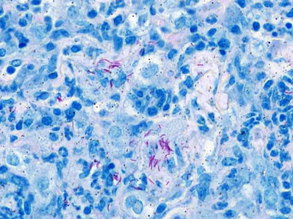

Explaining the Leak